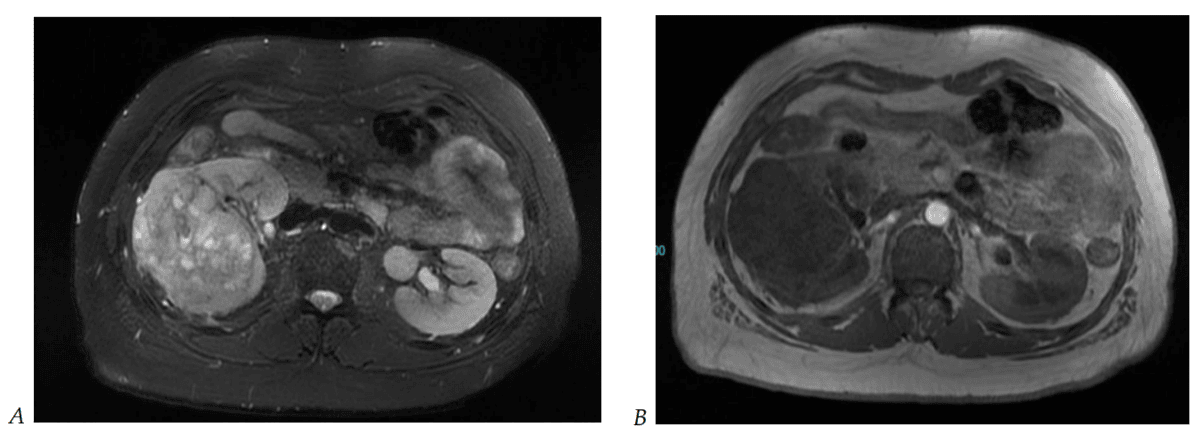

Clear-cell renal cell carcinoma (RCC) typically appears very bright on T2-weighted MRI, showing strong, often heterogeneous arterial enhancement after contrast administration42. It also displays low ADC values on diffusion sequences, reflecting its high cellularity. A thin, dark pseudocapsule may also be visible, aiding in the distinction of this aggressive subtype43.

Angiomyolipoma (AML) is identified by signal dropout of macroscopic fat on fat-suppressed T1-weighted images, while classic AMLs appear bright on T2, but fat-poor or hemorrhagic AMLs lack visible fat and may resemble malignant masses47.

Cystic lesions classified as Bosniak II-IV are characterised by complex internal structures, including septations, mural nodules, or irregular walls48. MRI allows for the confident detection of contrast wash-in or enhancement on subtraction images, with Bosniak III/IV cysts carrying a higher malignancy risk.